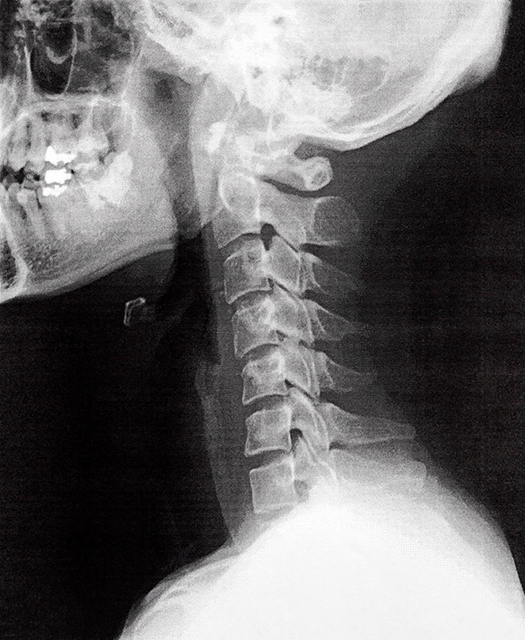

首の寝違えたような痛みと他疾患との見極め

首の寝違えたような痛みが長引く場合、頸椎椎間板ヘルニアや神経根症など、別の疾患が関与していることがあります。自己流の治し方を続けても改善しない場合は、画像検査や神経学的検査を受けることで正確な診断が可能です。首にしびれや腕の脱力がある場合、寝違えたような痛みだけでなく重大な疾患が隠れている可能性があるため、早期に医師へ相談する治し方が必要です。